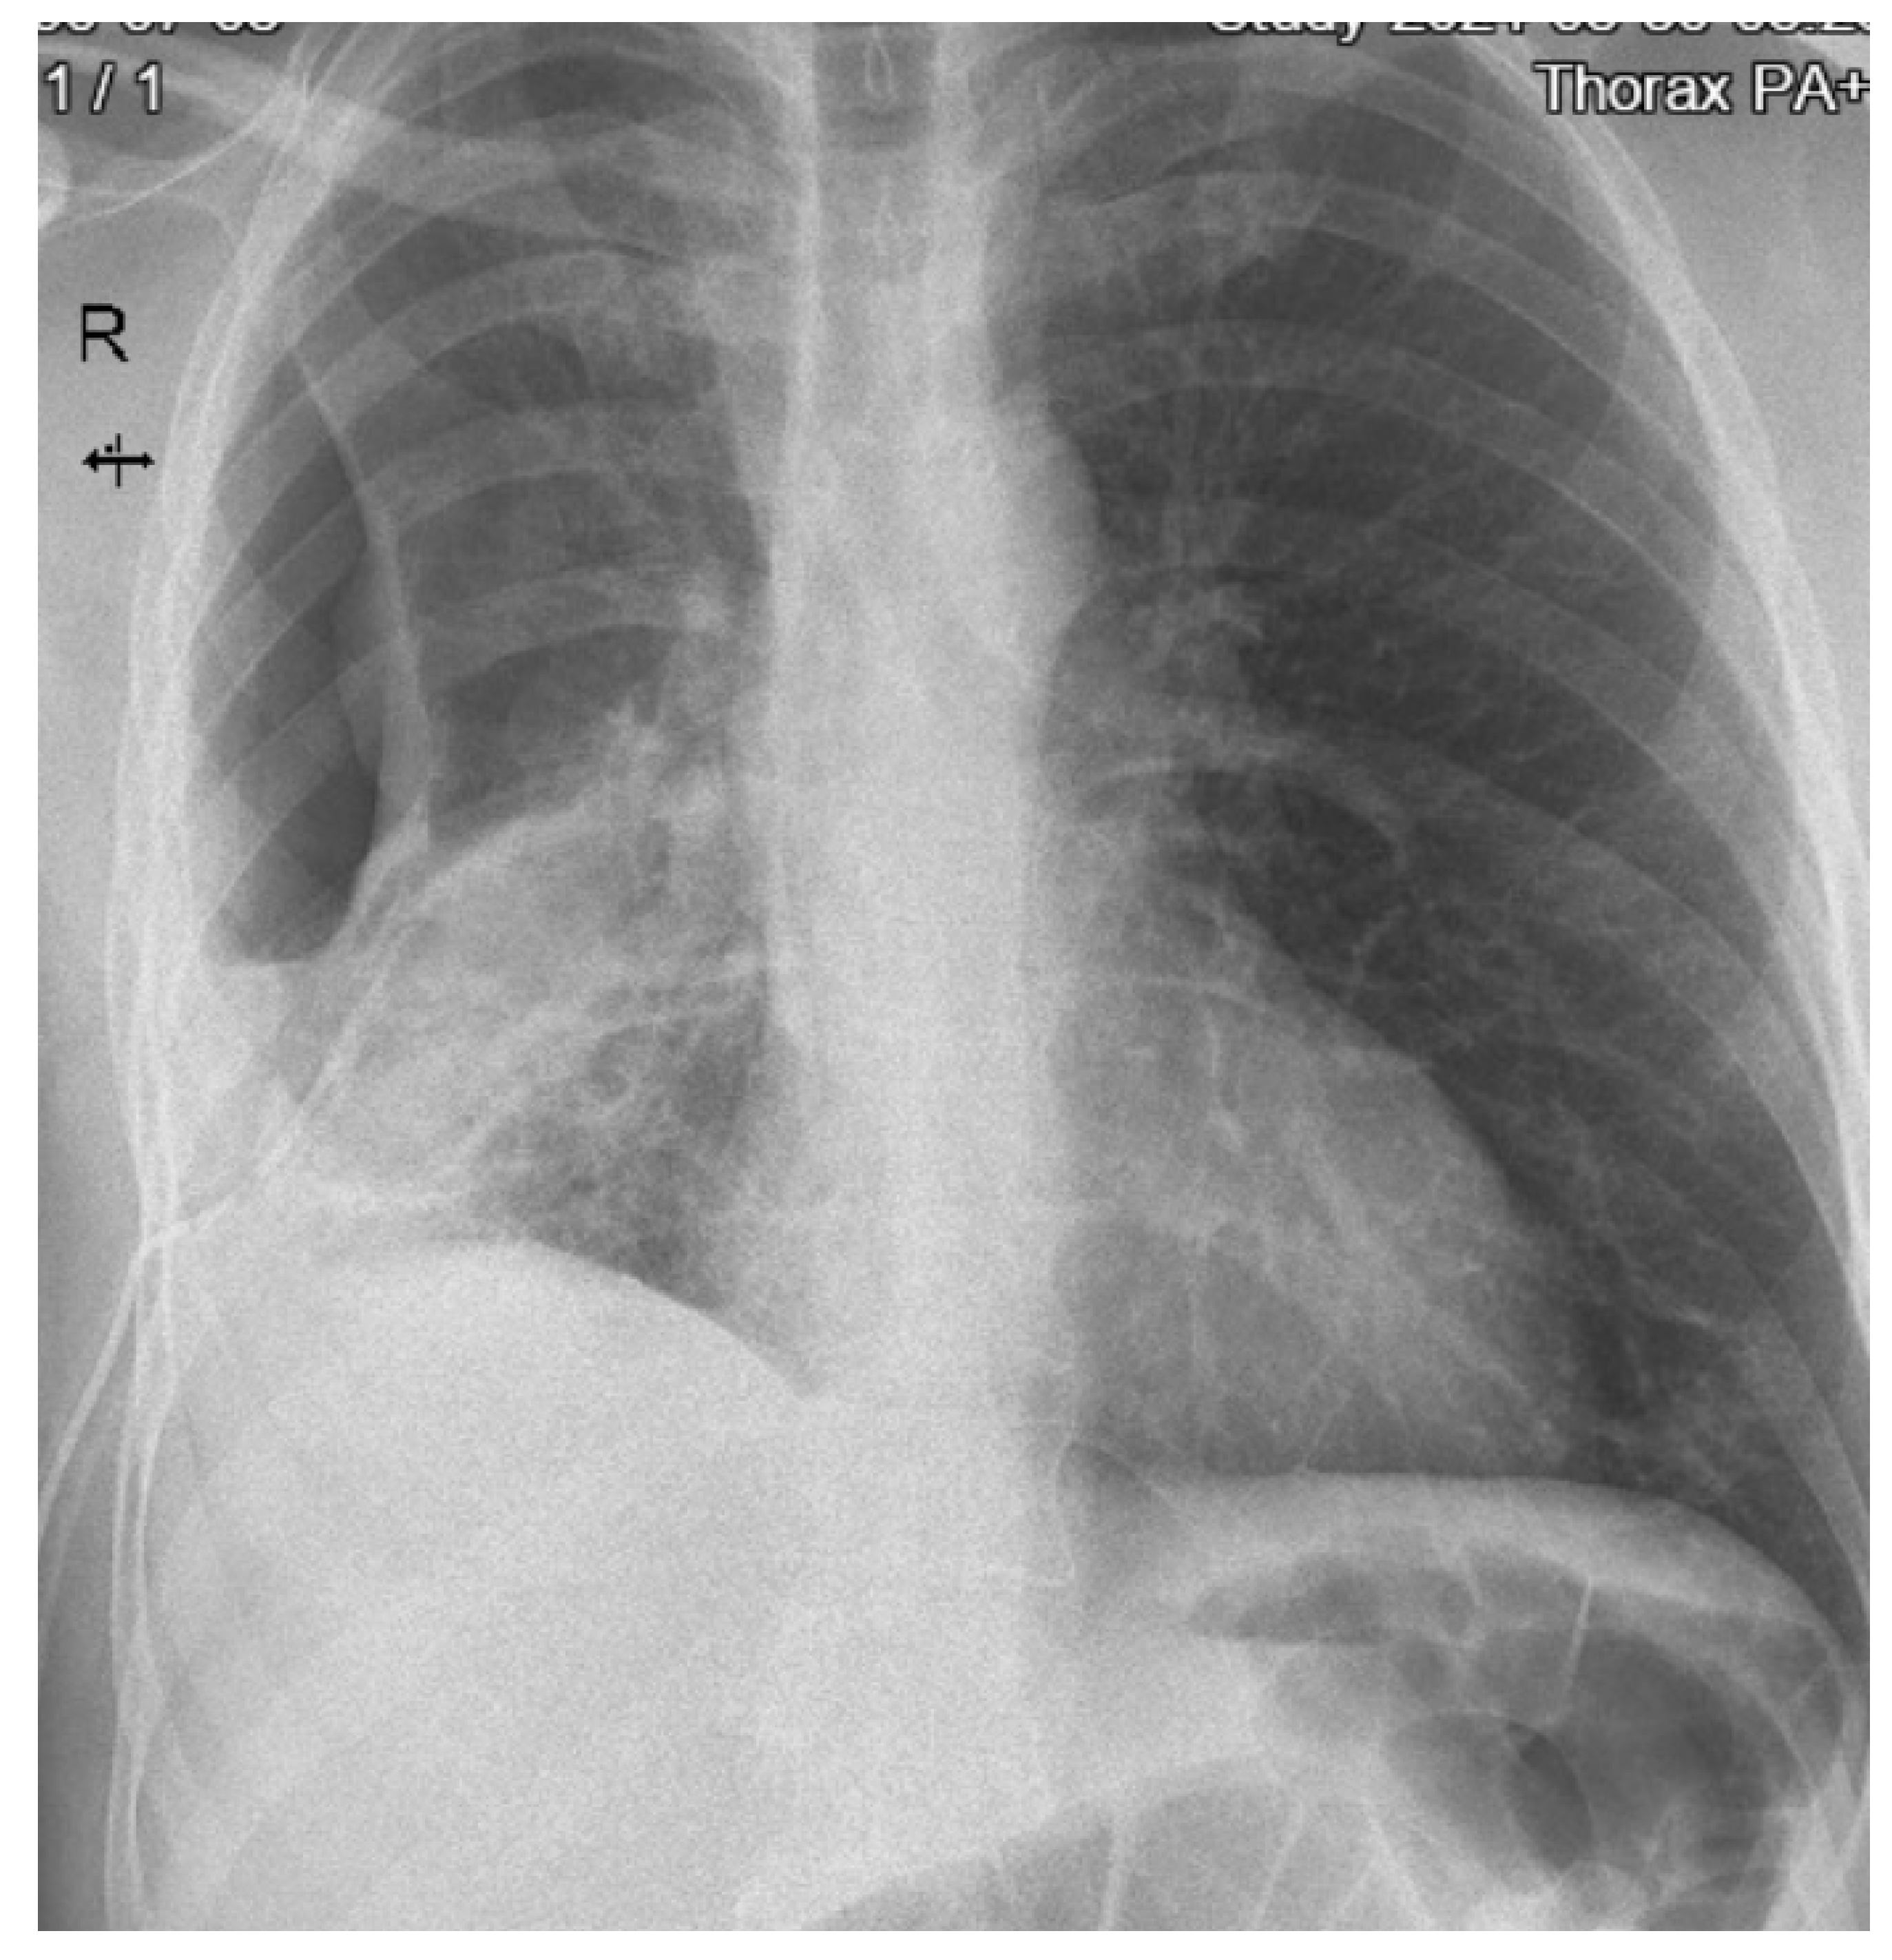

On the fourteenth day, the number of leucocytes and inflammatory markers continued to increase (L = 42.000 cells/mm3, ESR = 30 mm/1 h, C-reactive protein = 102 mg/L) and the chest X-ray found reticulomicronodular opacities with pleural effusion on the right (Figure 2).

Figure 2. Chest X-ray (day 14) showing pleural effusion.